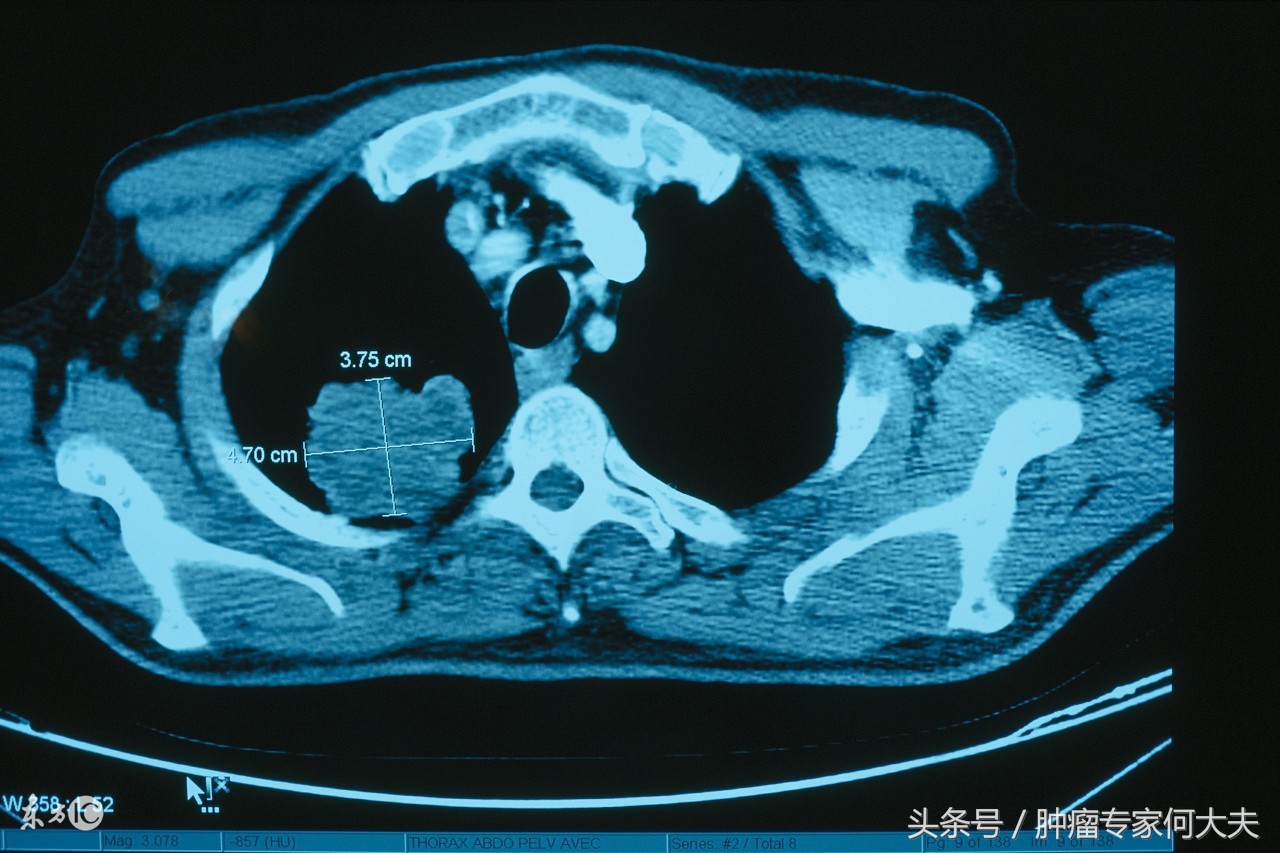

王先生,今年57岁,辽宁省葫芦岛市人,12年前因为咳嗽在当地医院呼吸科诊断为变异性哮喘,医生给予激素、支气管舒张剂等药物治疗,很快就能缓解,但每年逢秋冬季节,都得犯一次病,有时候一年犯两到三次,每次犯病医生给的药都很给力,由于成了“*毛老**病”,所以王先生自己以及他的医生都有惯性思维了,但就在2015年11月初,王先生再次“犯病”了,他的医生对他的病很熟悉,仍然按照“*毛老**病”处理,可这次处理完他缓解不明显,咳嗽很剧烈,为刺激性干咳,夜里入睡都成问题。持续了将近3周,医生建议他查胸部CT看看,结果让王先生和他的医生惊呆了,“右肺占位性病变,伴两肺多发小结节影,多发纵膈淋巴结肿大,考虑淋巴结转移,建议进一步检查”。经过气管镜和全身PET-CT检查,诊断为右肺鳞癌,IV期。确诊肺癌晚期的王先生,非常绝望,对他的医生也非常不满,后来一度将多年为他诊病的医生告上了法庭,但法庭认为王先生患有明确的“变异性哮喘”旧病,医生第一时间的处理按照经验性治疗不构成医疗差错和漏诊,后来这事就不了了之了。

右肺癌